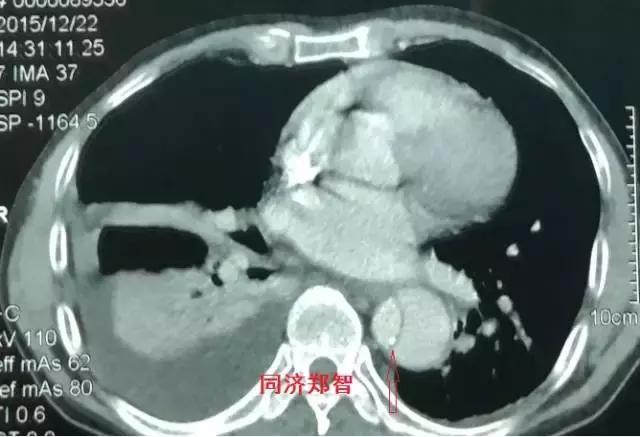

病例四

腹部平扫CT提示腹主动脉增宽,CTA证实为腹主动脉局限性夹层(红箭头所示)。